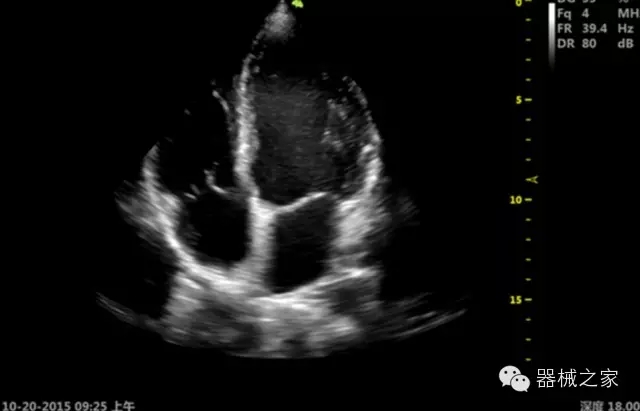

品牌:飛依諾(VINNO)

公司簡介:

飛依諾科技(蘇州)有限公司2010年在蘇州工業(yè)園區(qū)成立,公司致力于成為世界一流醫(yī)療超聲品牌。核心創(chuàng)始團(tuán)隊(duì)囊括了來自于全球著名公司十多位資深研發(fā)和市場人才,均為業(yè)界精英。

官方網(wǎng)站:www.vinno.com

經(jīng)典產(chǎn)品:VINNO 6

臨床圖片賞析

產(chǎn)品特點(diǎn)

·ICU/CCU;

·飛依諾特有心臟純凈波探頭提供更好的穿透力和彩色敏感度,以及結(jié)合TView梯形拓展改善困難病人深部組織成像;

·獨(dú)有RF敏感血流使得心臟血流完美呈現(xiàn);